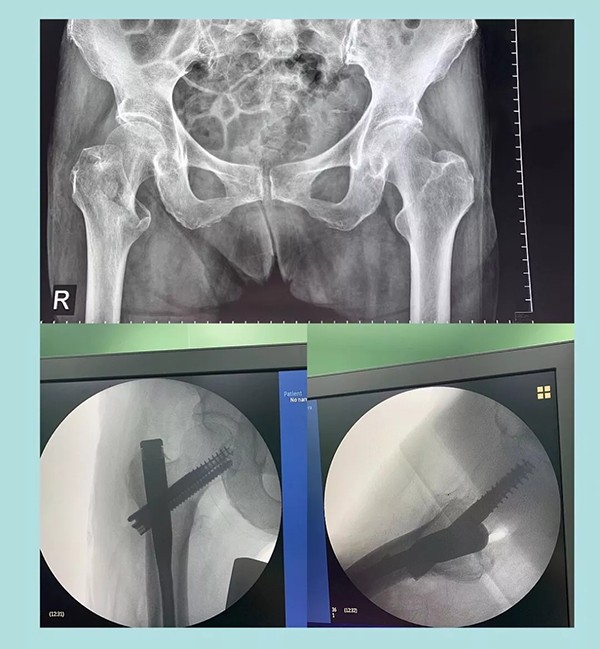

幾天前,蒲奶奶不小心摔了一跤倒地不起,到家附近醫(yī)院檢查后被診斷為右側(cè)股骨粗隆粉碎性骨折。醫(yī)生告知家屬,這種骨折對于老人來說非常棘手,建議保守治療。為提高老人生活質(zhì)量,家人商量后決定放手一搏,在打聽到我院關(guān)節(jié)科對這種病例治療效果非常理想后,立即轉(zhuǎn)往我院。

經(jīng)過內(nèi)科疾病的治療調(diào)理,總體符合手術(shù)條件后,羅軍主任帶領(lǐng)手術(shù)團隊為老人實施了閉合復(fù)位Intertan髓內(nèi)釘微創(chuàng)手術(shù)。為避免全麻對肺功能的影響,術(shù)中沒有使用常規(guī)的全麻氣管插管,而是采取神經(jīng)阻滯麻醉。術(shù)前老人嚴重貧血,為盡可能減少術(shù)中出血,手術(shù)采用微創(chuàng),且在半個小時內(nèi)順利完成。術(shù)后老人沒有明顯疼痛,術(shù)后一周即下地行走。